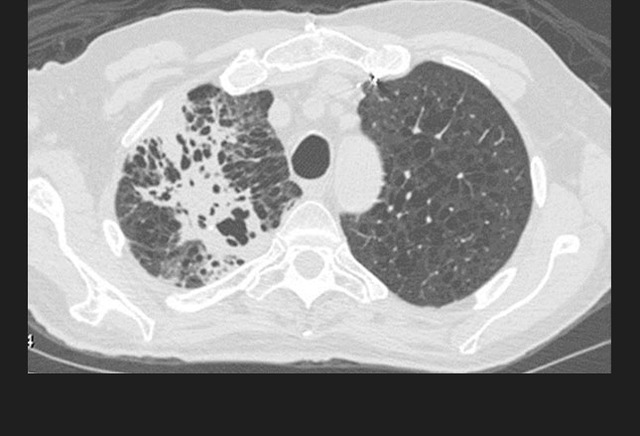

图2. 无数的肺部小结节,与粟粒型肺结核表现一致

初次感染结核常为隐匿性经过,少数患者可能会有明显的血液播散,导致粟粒型肺结核。